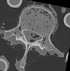

Case 28: In vitro vertibral body CT (intra subject)

Case 39: : In vitro thoracic vertebrae CT (intra subject)